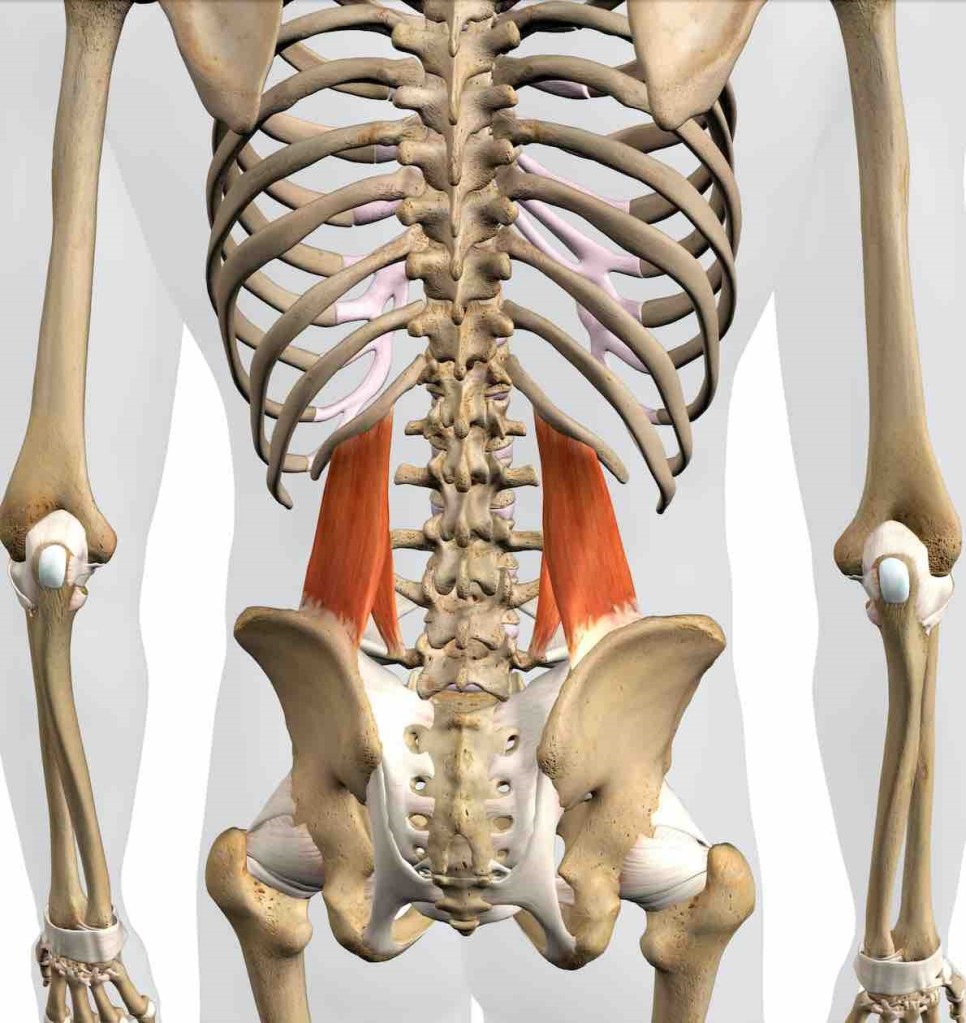

En el síndrome de ACNES, aparece un dolor abdominal, paraumbilical, que se produce en las ramas terminales de los nervios intercostales 8-12 que aparecen atrapados entre los músculos abdominales, produciendo dolor neuropático crónico de difícil diagnóstico.

El signo de Carnett es una maniobra de exploración del dolor abdominal, utilizada para diferenciar el dolor originado en la pared abdominal del dolor de los órganos internos, el dolor visceral. Es positivo si el dolor aumenta o persiste cuando el paciente contrae la musculatura abdominal, al incorporarse del decúbito, mientras se presiona el punto de dolor.

También la realización de una ecografía de la pared abdominal puede detectar anomalías o engrosamientos en la vecindad de las ramas terminales de los nervios intercostales y reforzar la sospecha diagnóstica.